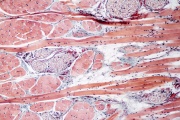

| 15:12, 30 בנובמבר 2017 | Pompe1.jpg (קובץ) |  |

723 קילו־בייטים | Motyk | 1 | |